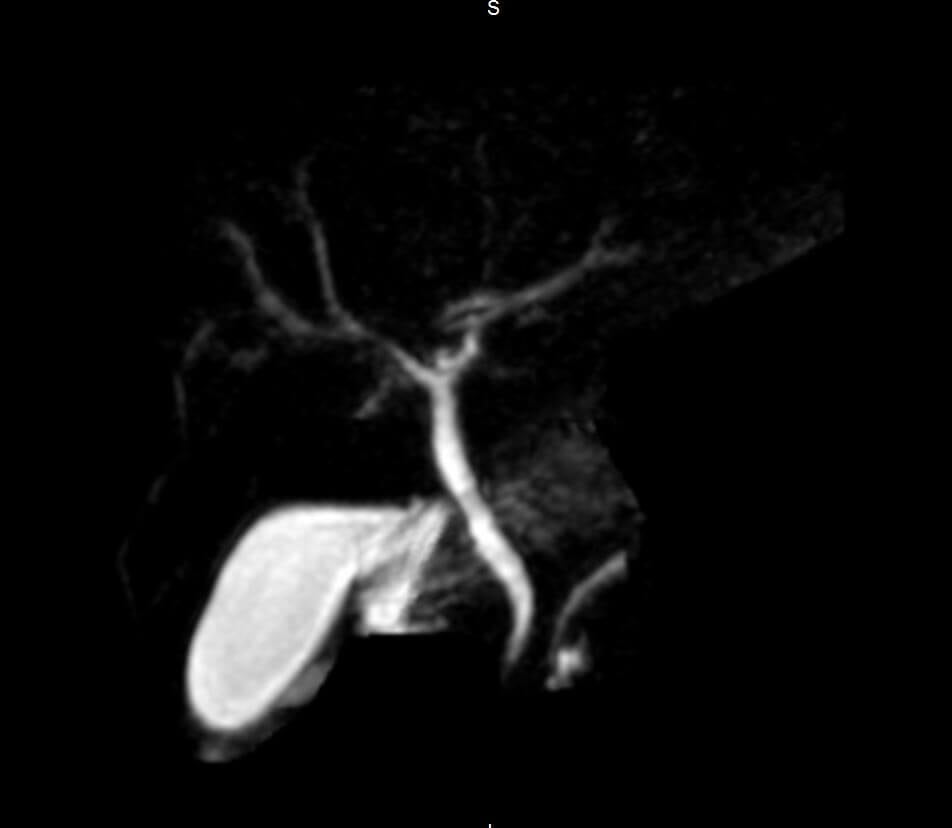

from radiopaedia.org

Choledocholithiasis Radiology Reference Article